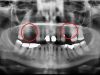

• до синус-лифтинга

• после синус-лифтинга

• после установки имплантатов в верхнюю челюсть